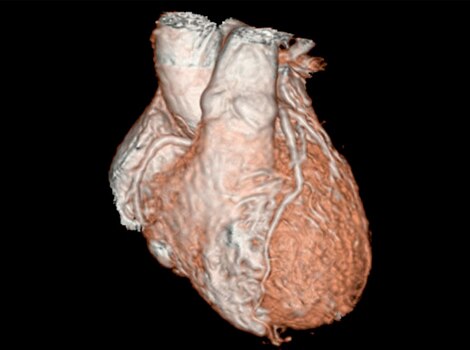

3D Heart

借助鲜血、3D 序列实现解剖结构和心脏血管的可视化。

Revolution CT & CardioGraphe4

无论是否服用了 β 受体阻滞剂,可在任何心率下针对成像或综合心脏评估实现单次心跳、全心采集。5

借助鲜血、3D 序列实现解剖结构和心脏血管的可视化。了解更多信息